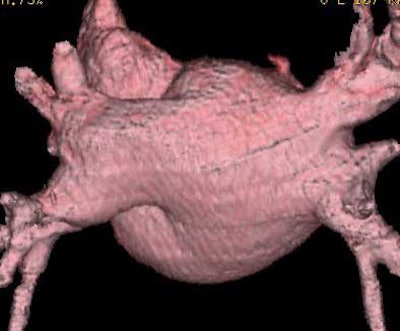

![]() |

| Endocardial (above) and epicardial (below) views from a patient with an accessory vein on the right (which happened to be vein that drained the right middle lobe (RML) and superior segment right-lower lobe (ssRLL), as well as separate LS and LI veins (left side seen in epicardial view only), for a total of five pulmonary veins. Images courtesy of Dr. Joan Lacomis. |

Endocardial volume-rendered views of the right and left pulmonary inflow vestibules show the imaging volume from the intra-atrial perspective. They are useful for assessing global size, the shape and volume of the left atrium, the number of veins, accessory veins, and conjoined veins, and for examining the ostial branches and their intravenous saddles, the region of the atrial wall interposed between separate ipsilateral pulmonary veins.

Epicardial volume-rendered views should include the left atrium and the distal third of the pulmonary veins, but not the heart, pulmonary arteries, aorta, or vena cavae, in order to show the relevant structures without their being obscured by the adjacent anatomy.